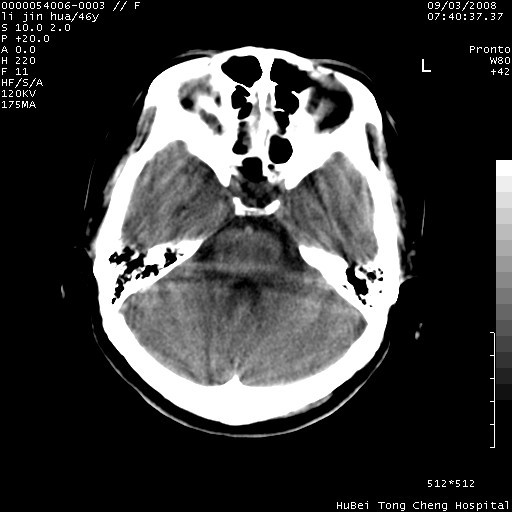

以下是引用panyishengct在2008-9-6 1:47:00的发言:[br]病史?[br]左侧枕/顶叶见一等/低混杂密度占位,壁完整,厚薄较均匀,其前方似有一类似小病灶,周围有水肿带,请结合病史考虑,脓肿可能,不排外转移瘤或胶质瘤,建议增强扫描。